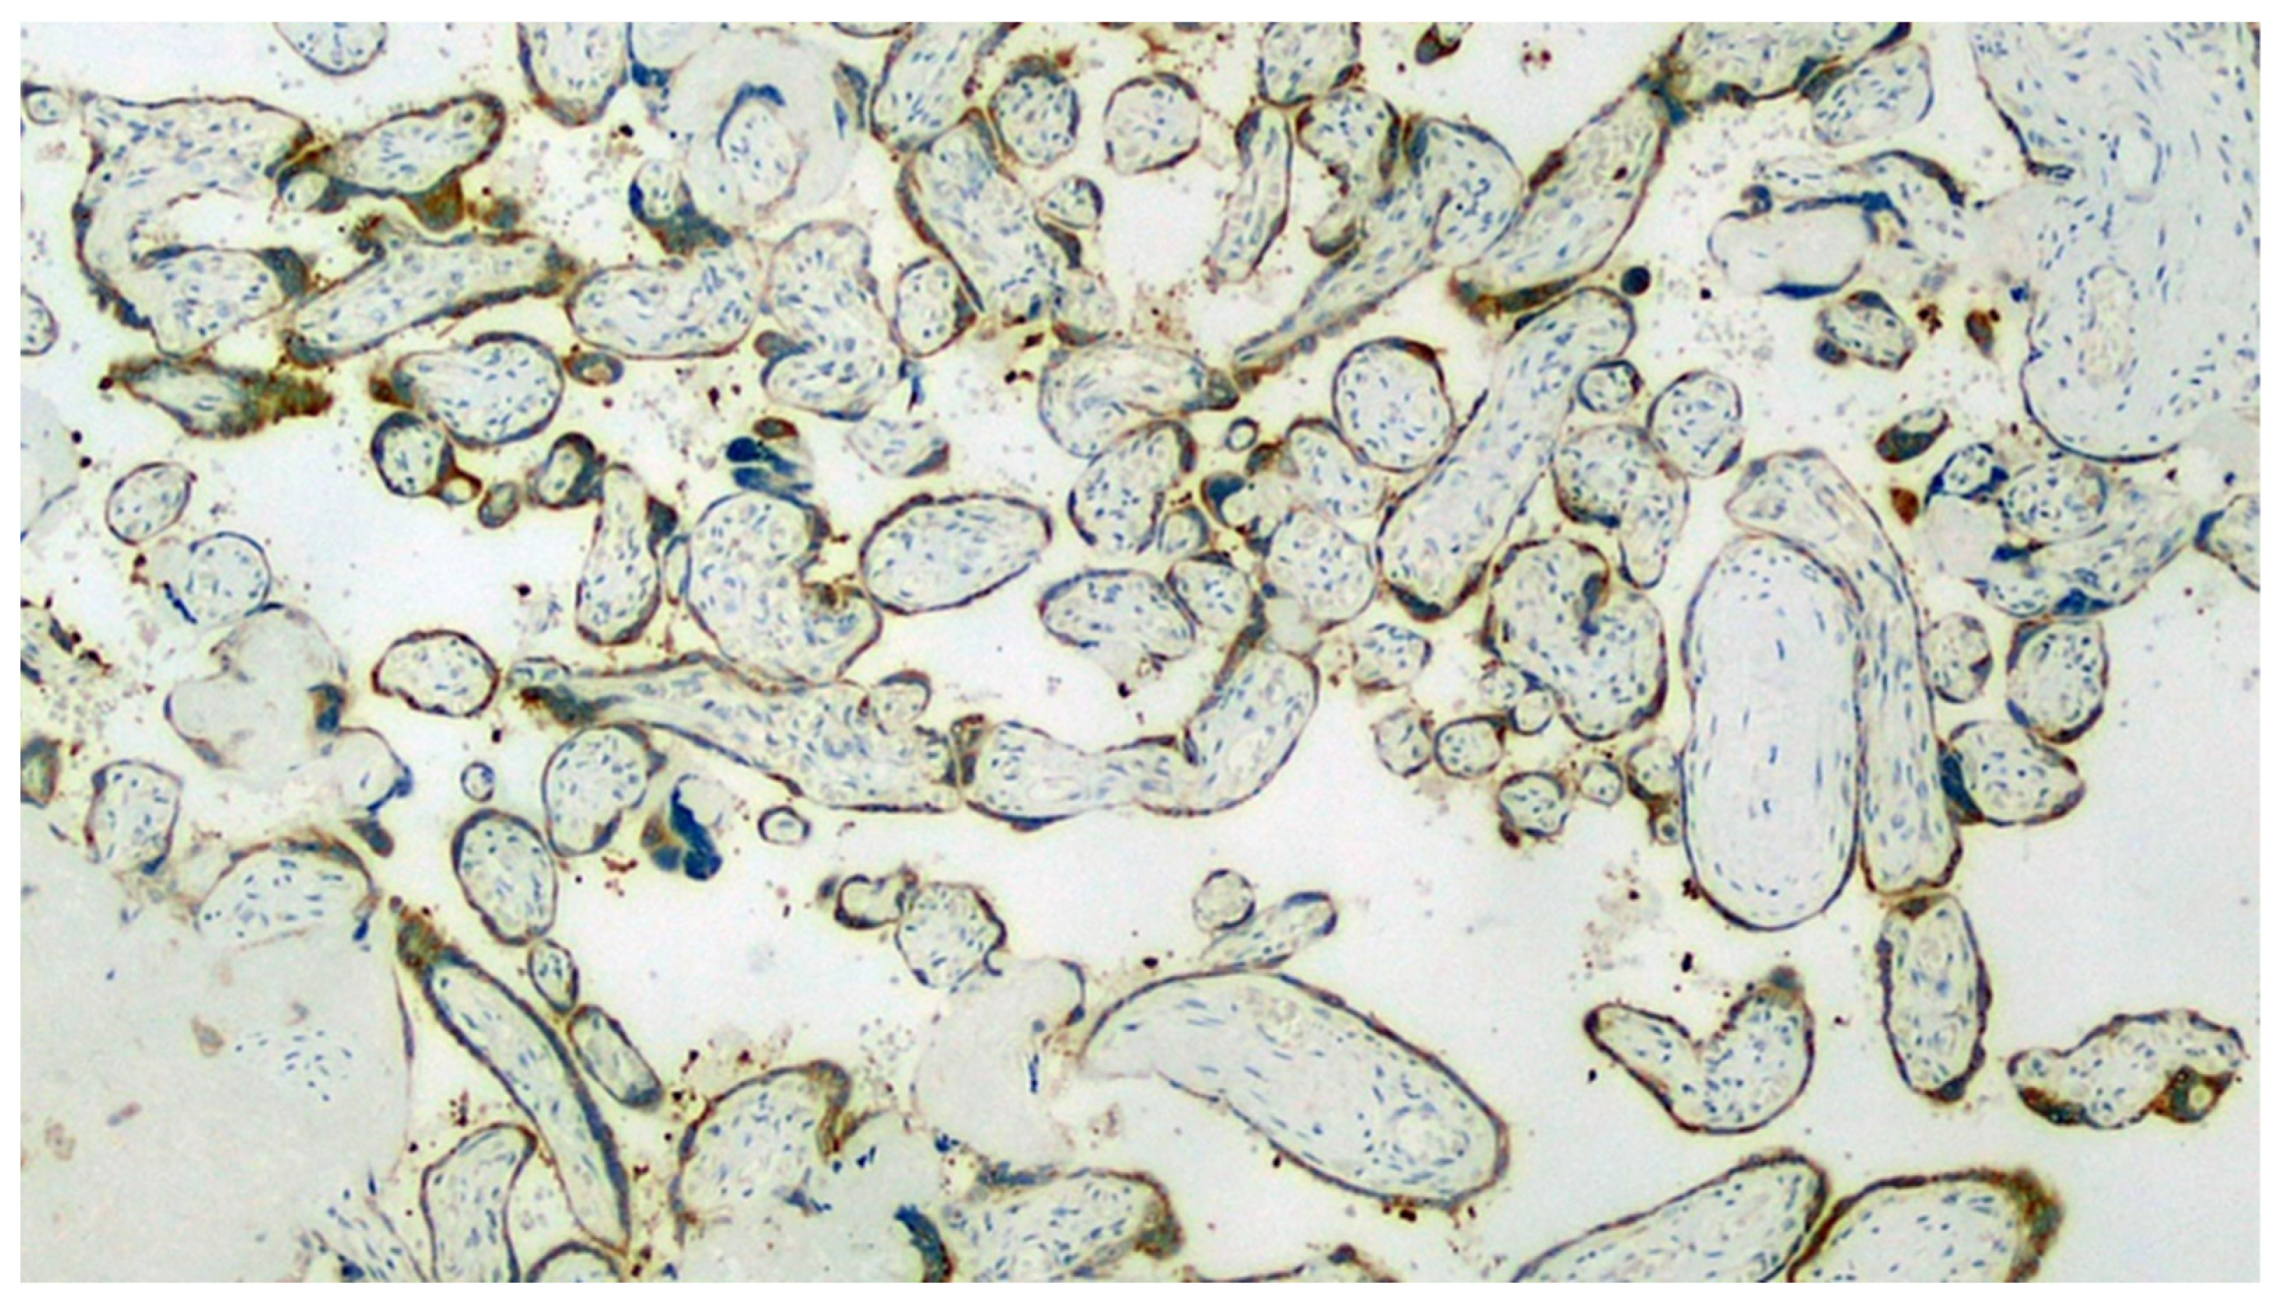

Figure 8.

Expression of viral antigen in stromal cells of the basal decidua (IHC, 400×).

Figure 9.

Detail of a small vessel of an 8th order main villus characterized by the expression of a spike glycoprotein antigen on endothelial cells degenerated during thrombosis (IHC, 400×).